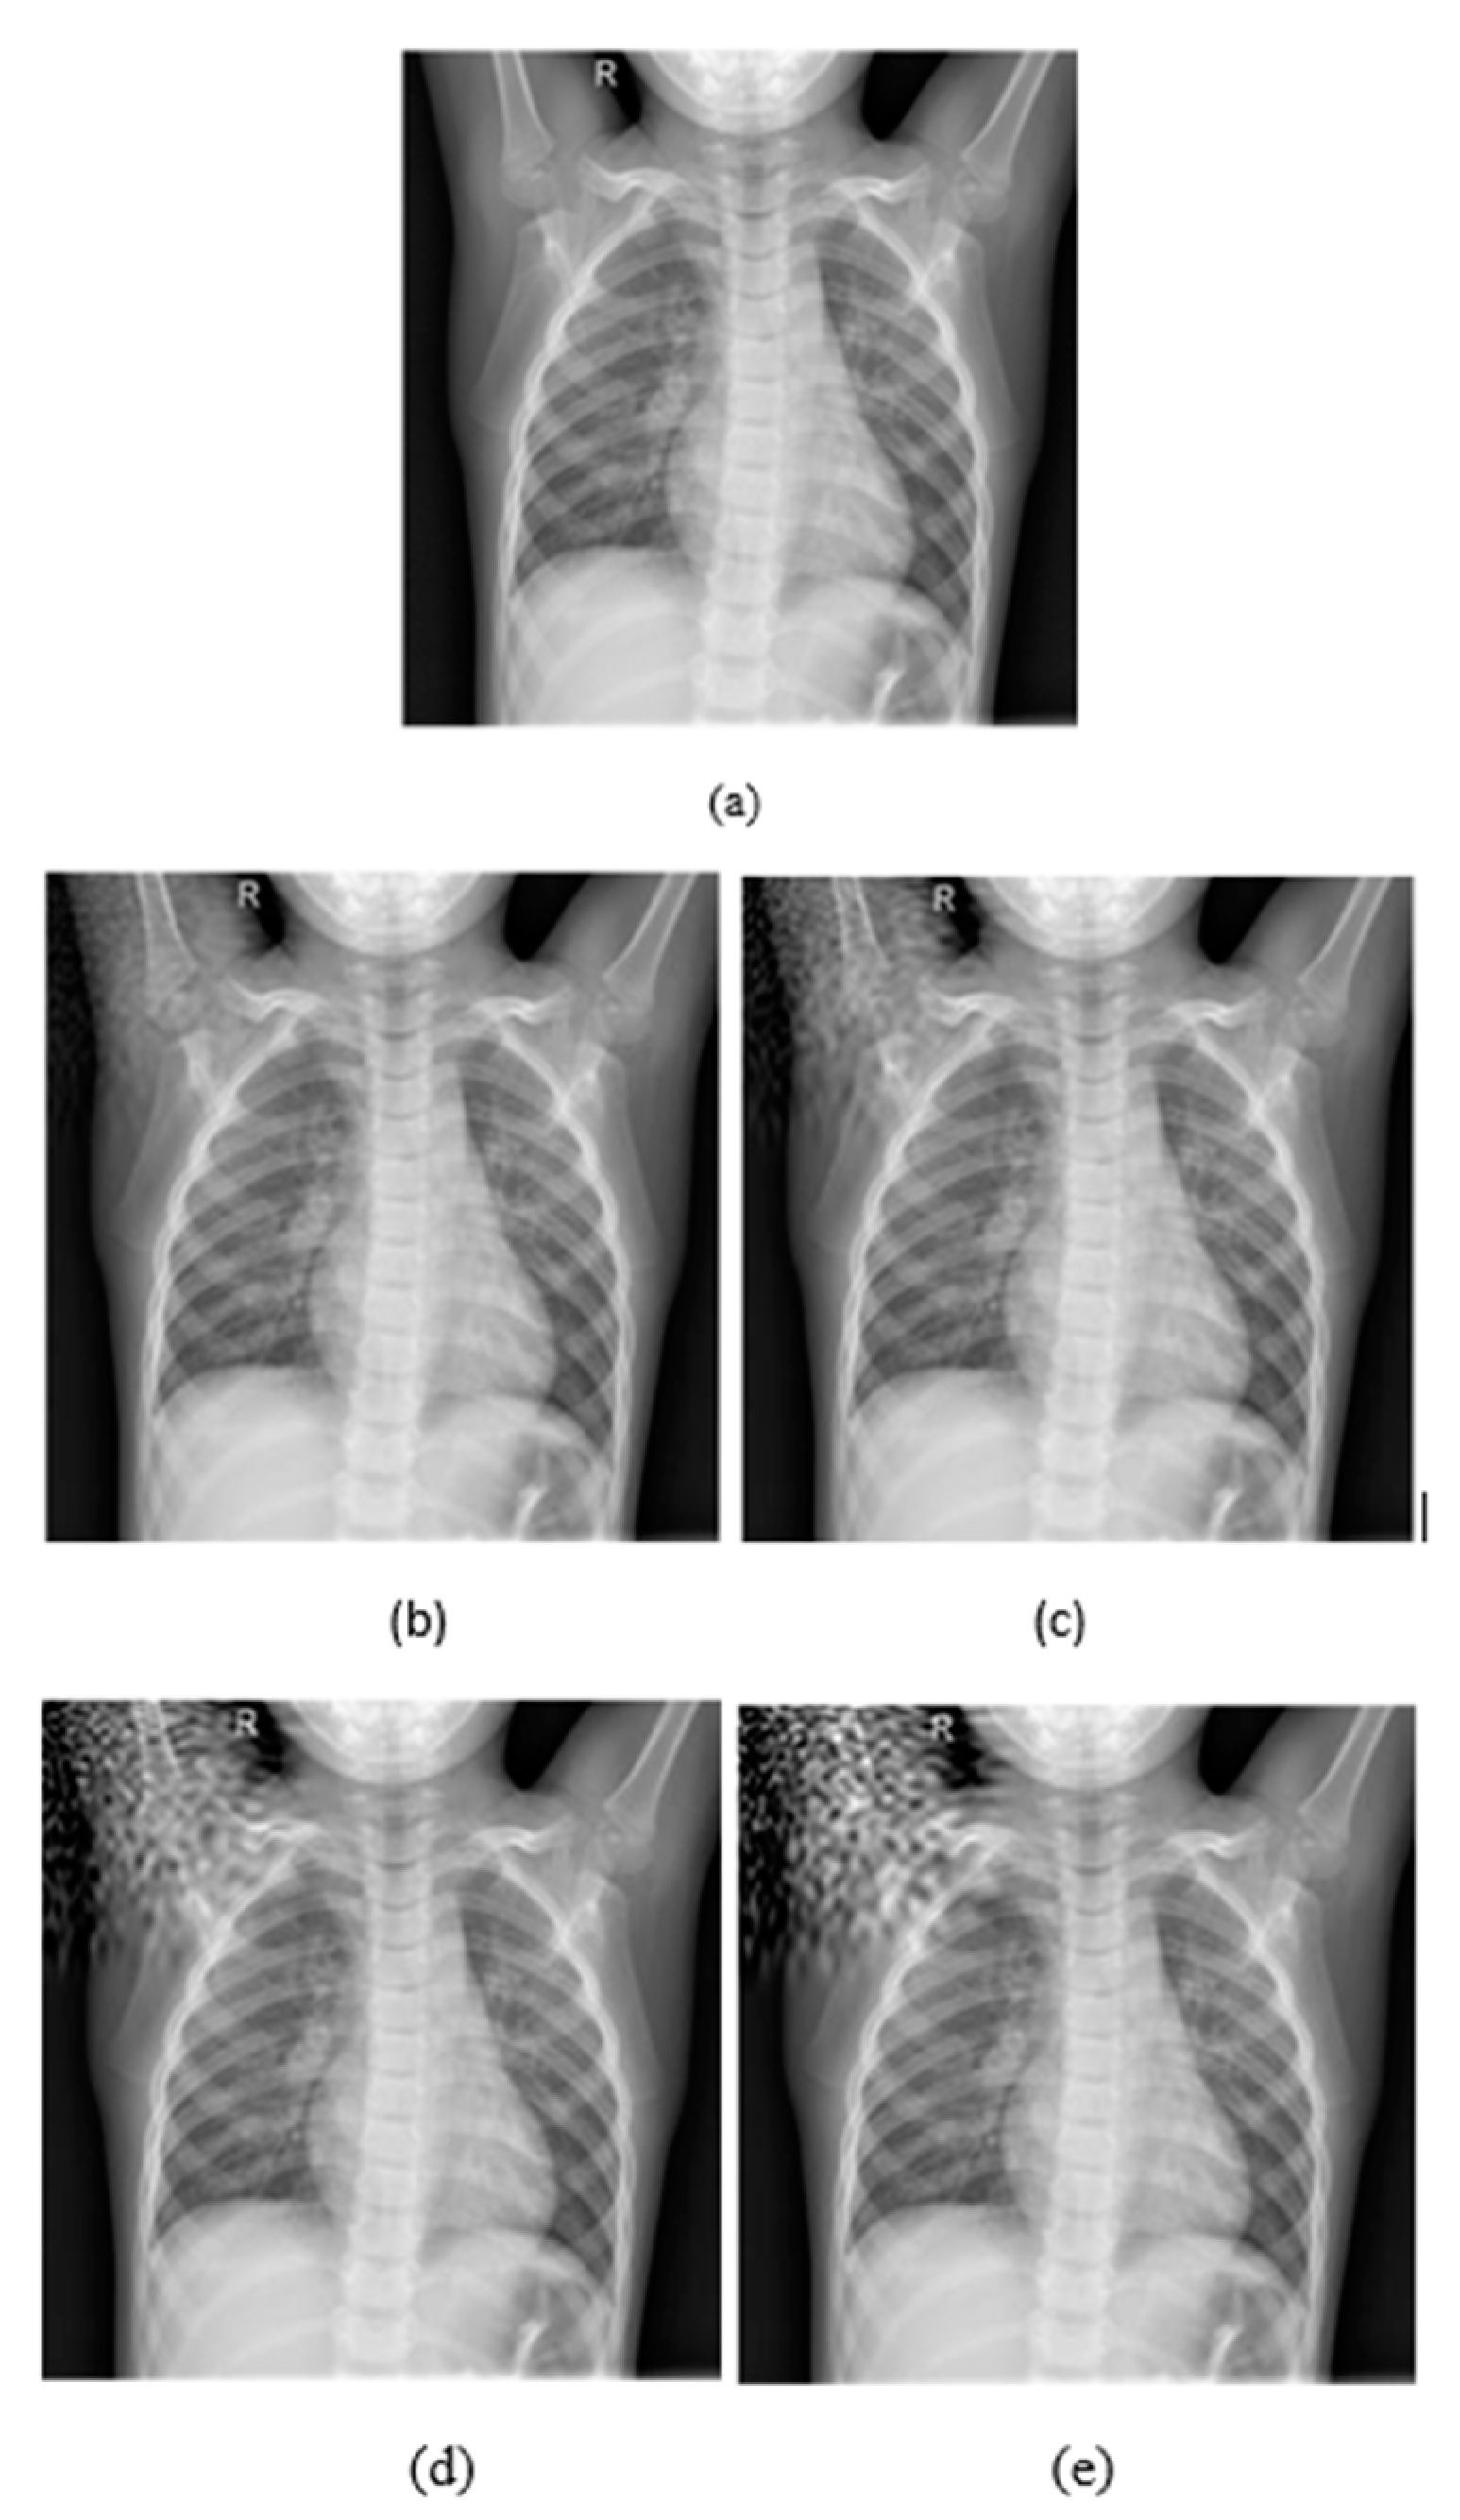

4.1. Datasets